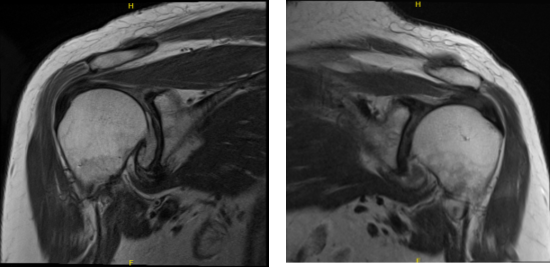

MRI of Left and Right Shoulder

To understand better the condition of her shoulders we decided to take an MRI. Left shoulder MRI impression as follows: Supraspinatus tendinosis with low-grade partial-thickness articular sided tearing. Degeneration of the acromioclavicular and glenohumeral joints.

Truncation of the free edge posterior superior glenoid labrum. Moderate glenohumeral joint effusion. Tendinosis and tenosynovitis of the long of the biceps tendon. Right MRI impression as follows: Degenerative changes of the acromioclavicular and glenohumeral joints. Supraspinatus as with high-grade partial-thickness articular sided tearing. Tear of the posterior superior labrum.